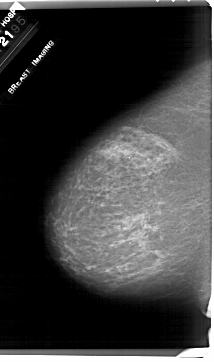

A_1917_1.RIGHT_MLO

LEFT_MLO LINES 6361 PIXELS_PER_LINE 3901 BITS_PER_PIXEL 12 RESOLUTION 43.5 NON_OVERLAY